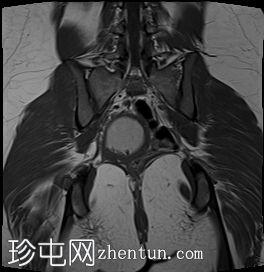

冠状位

T1加权像

子宫腔重复畸形,表现为两个子宫体和两个宫颈。

右侧宫颈和子宫腔明显扩张,内部血流信号显示中央狭窄,T1加权像呈高信号,T2加权像呈低信号,脂肪抑制序列图像上无信号下降,内部可见持续低信号灶。最大轴位和冠状位直径分别为约6.5 x 6.4 x 14.2 cm。可见该肿块向前压迫膀胱,向后推移右侧卵巢,并紧贴左侧宫颈。

双侧重复子宫腔的交界区完整,未见明显的肌层局灶性病变。左侧子宫内膜厚度正常。

可见两个阴道腔,共同远端开口长1.6厘米。

左侧卵巢囊肿最大轴径和头尾径分别约为5.7 x 4.3 x 5.5厘米,T2加权像呈高信号,T1加权像呈低信号。

双侧卵巢卵泡形态正常。未见附件实性或囊性肿块。